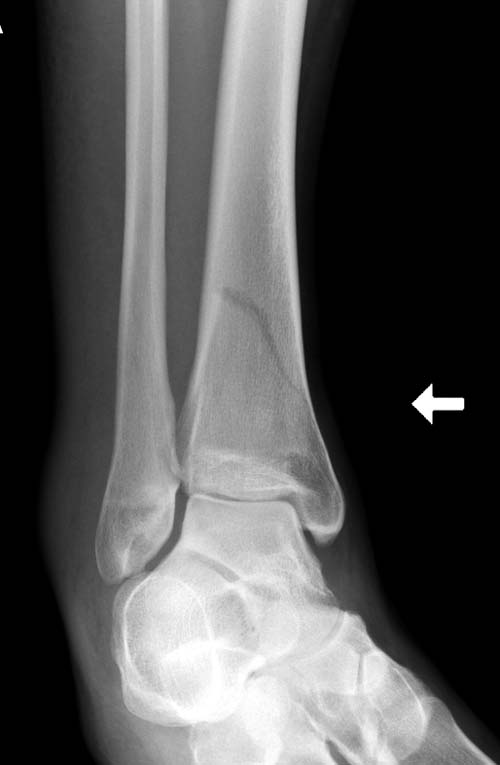

Второй случай в результате скоростной травмы, кроме пилона, вовлечение

других органов! Отек при поступлении и открытый перелом на другой

стороне. В таких случаях нет смысла спешить, и временный наружный

фиксатор на несколько дней. После спадения отека фиксация

передне-наружной пластиной.  Реабилитация - ранние движения, без

нагрузки.